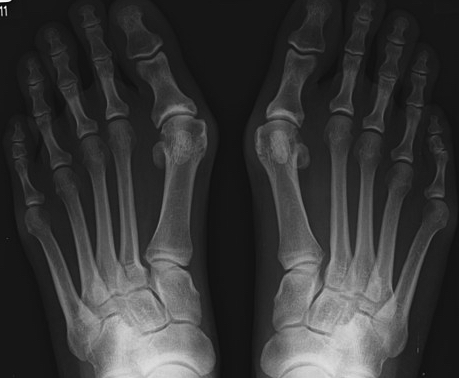

무지외반증이란 엄지발가락의 변형과 그로 인한 관절의 통증을 일컫는 질환이에요. 무지, 즉 엄지발가락이 새끼발가락 쪽으로 휘면 발 안쪽이 돌출되고 그 부위가 계속해서 신발과 닿게 되면 염증이 생기고 통증이 유발되어요.

무지외반증은 엄지발가락 뼈가 흉하게 돌출되기 때문에 미관상 좋지 않은 것은 물론이고 무지외반증 증상이 심한 경우 발가락 문제에 그치는 것이 아니라 무릎에 영향을 미칠 수도 있어요. 나아가 골반이나 허리, 척추 문제로까지 이어질 수 있고요. 따라서 무지외반증 증상이 나타났을 때는 미루지 말고 적극적으로 치료해주는 것이 중요해요.

무지외반증 증상은 첫째, 엄지발가락이 휘고 둘째, 발 내측 부위에 통증이 있으며 셋째, 통증 부위가 붉은색을 띄고 넷째, 엄지발가락을 제외한 나머지 발가락들이 저릴 수 있으며 다섯째, 제대로 걷기 힘들다 등으로 요약해볼 수 있는데요. 아래와 같이 무지외반증 증상을 네 단계로 나누어볼 수도 있어요.

1단계: 엄지발가락의 변형이 시작되고 통증이 간헐적으로 찾아옴.

2단계: 엄지발가락 변형이 더 진행되고 통증을 느끼는 빈도 또한 잦아짐.

3단계: 엄지발가락 변형이 심해지고 일상생활에 불편함을 느낄 정도로 통증이 커짐.

4단계: 변형된 엄지발가락이 두 번째 발가락과 겹쳐지는 교차변형이 생기고 인접한 다른 발가락에도 통증이 생김.